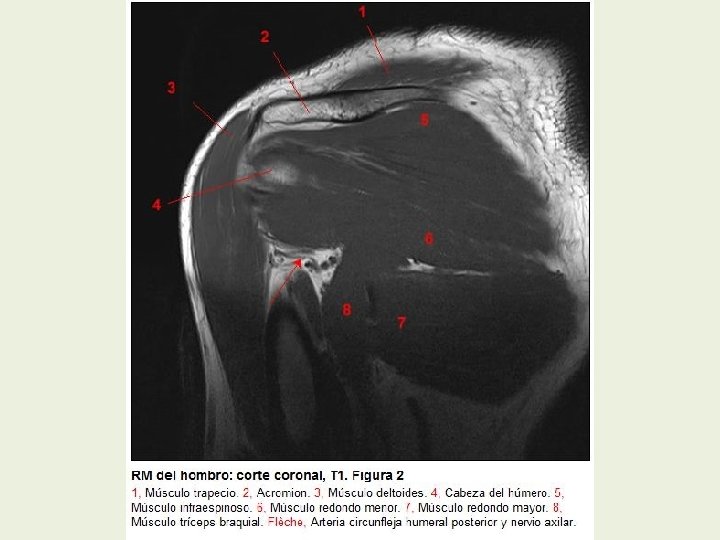

Hombro Cortes coronales RMN